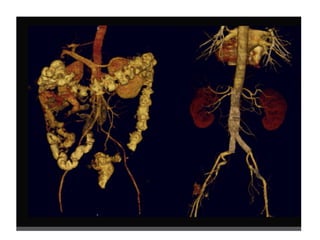

RECONSTRUÇÃO 3D

ANEURISMAS